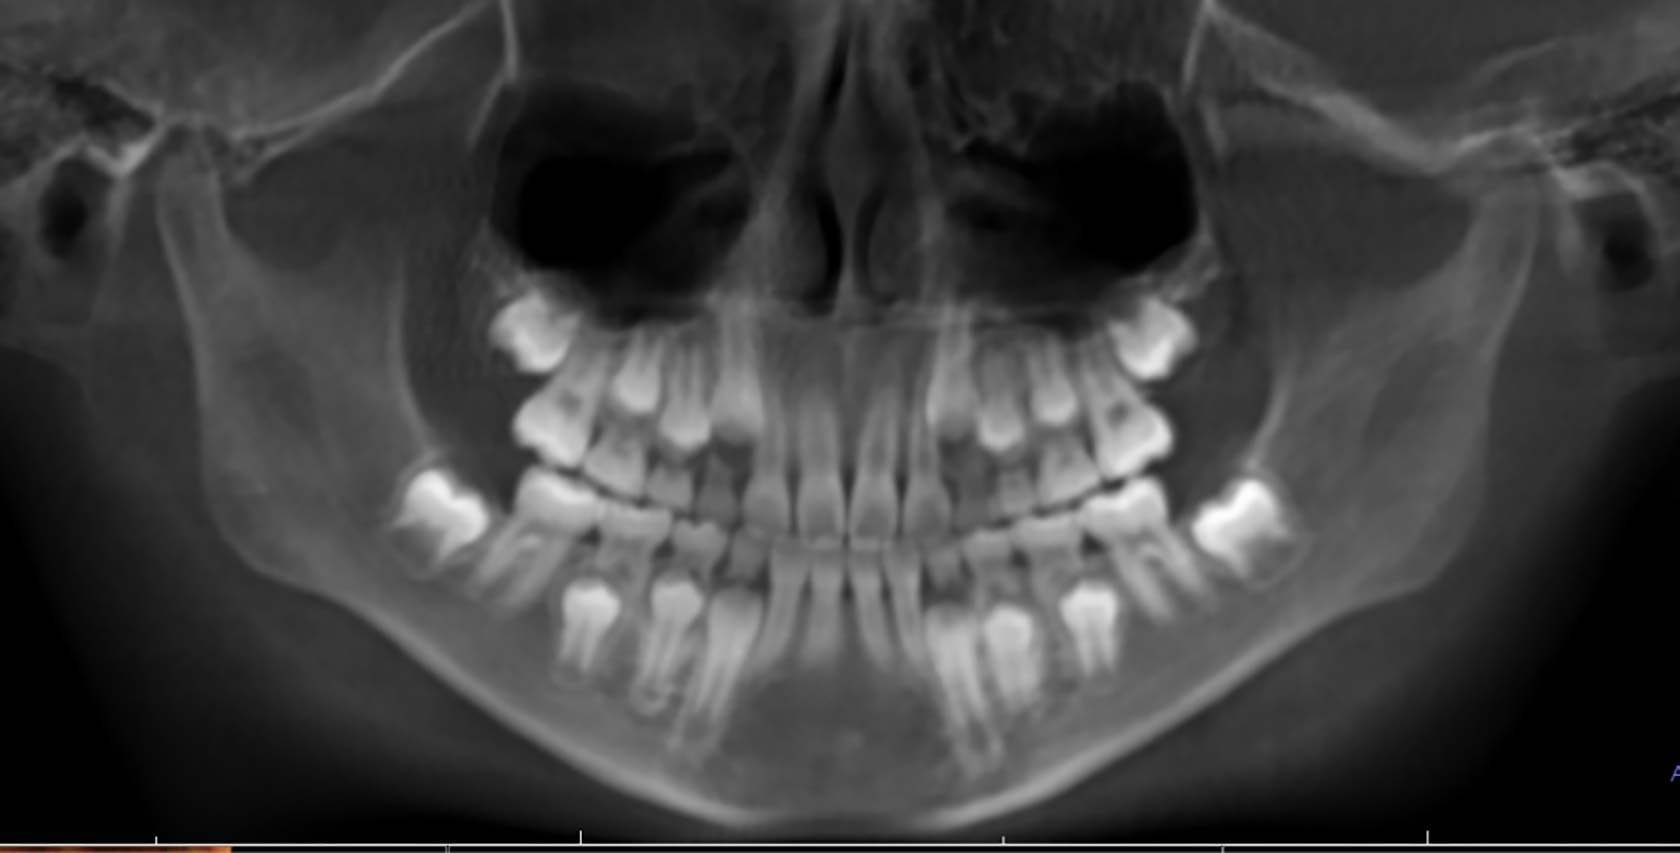

③レントゲン検査

(歯、顎の発育を診断します)

レントゲン写真を撮影し、各歯の状況や生え替わりの大人の歯の様子を確認します。なお撮影に使用する機器のX線量は従来のものの10分の1程度と非常に低いものですので、安心してお受けいただけます。